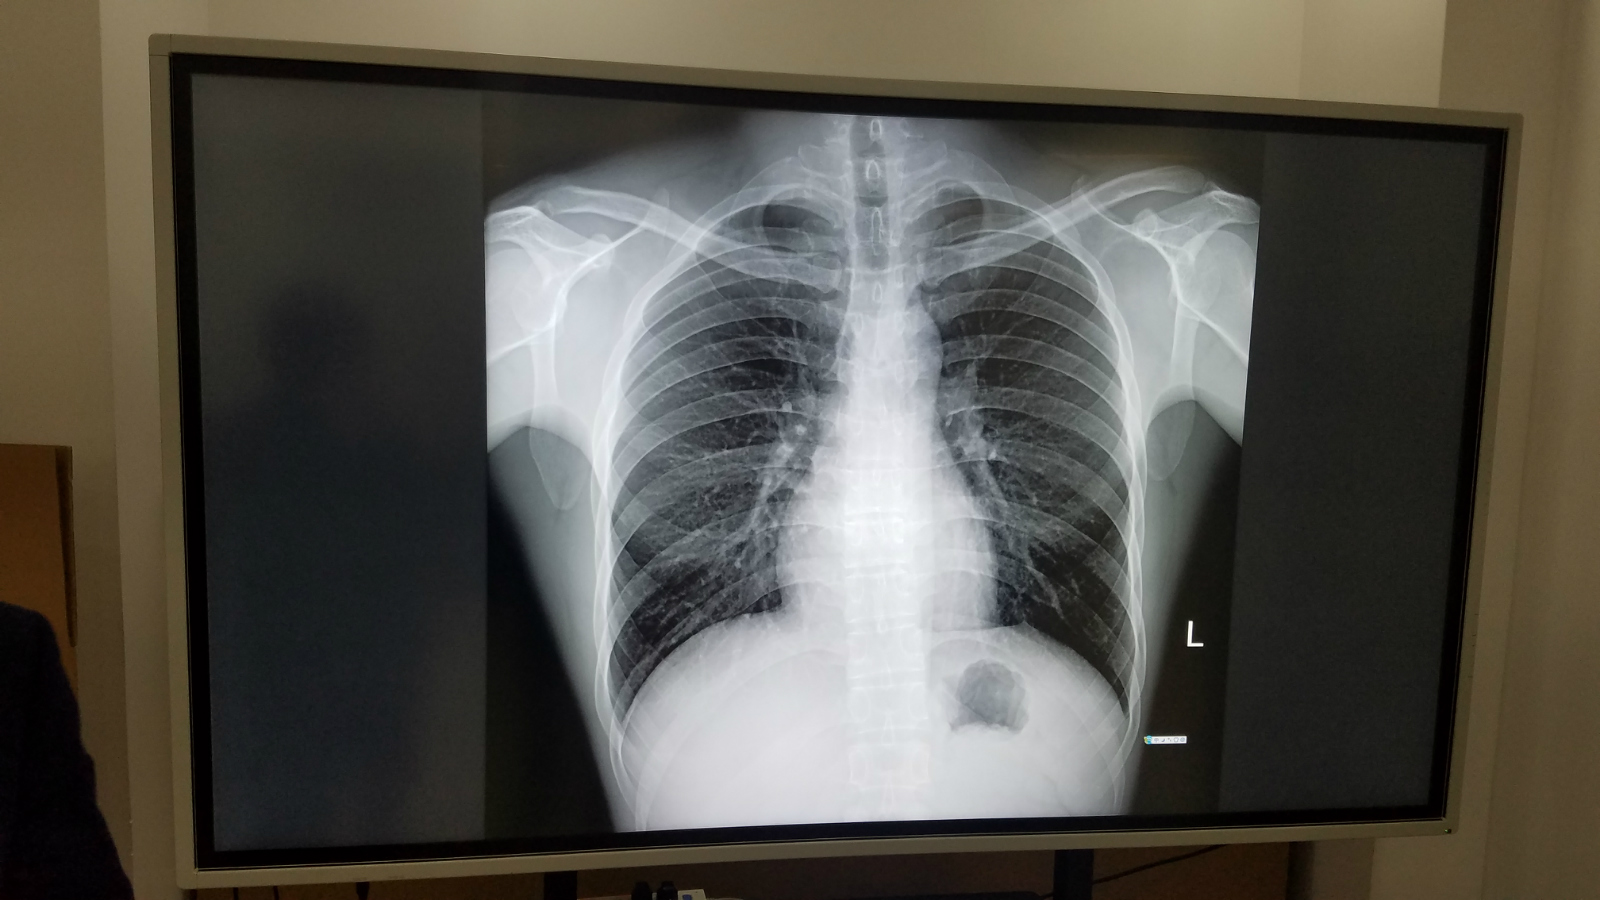

德恪商用本着“德行天下,恪尽职守,持续为客户创造最大价值”的理念,针对医院会诊,远程医疗,跨区域诊断,手术综合应用,医疗教学等应用场景而设计推出专业会诊大屏,尺寸涵盖:65寸,75寸,86寸,98寸,完全符合Dicom标准,满足医疗影像稳定一致的显示需求;具有超高分辨率、稳定亮度、忠实色彩还原、使用寿命长的优点; 支持一屏多显,可链接医院多种系统(如PACS、HIS系统),满足医院多种诊断及手术作业等需求。

小编这就带大家去看看DEKCO品牌98寸会诊大屏工艺展示实物拍摄效果:

德恪DEKCO会诊大屏无论是从功能实现上还是对灰阶显示参数指标,甚至信号接口,相较于商用显示器而已,无疑是提出了更高的要求,德恪商用由最初的“液晶显示系统解决方案提供商”的定位,现今添加了“医疗影像显示系统解决方案提供商”,给用户提供更优质,高品质的医疗会诊大屏解决方案。